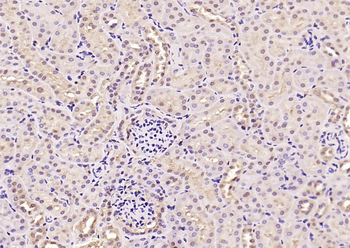

100 μl, 200 μl, 50 μlPhospho-Smad3 (Ser213) Rabbit Polyclonal Antibody [orb106193]

FC, IF, IHC-Fr, IHC-P

Bovine, Equine, Gallus, Guinea pig, Rabbit, Sheep

Human, Mouse, Rat

Rabbit

Polyclonal

Unconjugated

50 μl, 100 μl, 200 μl